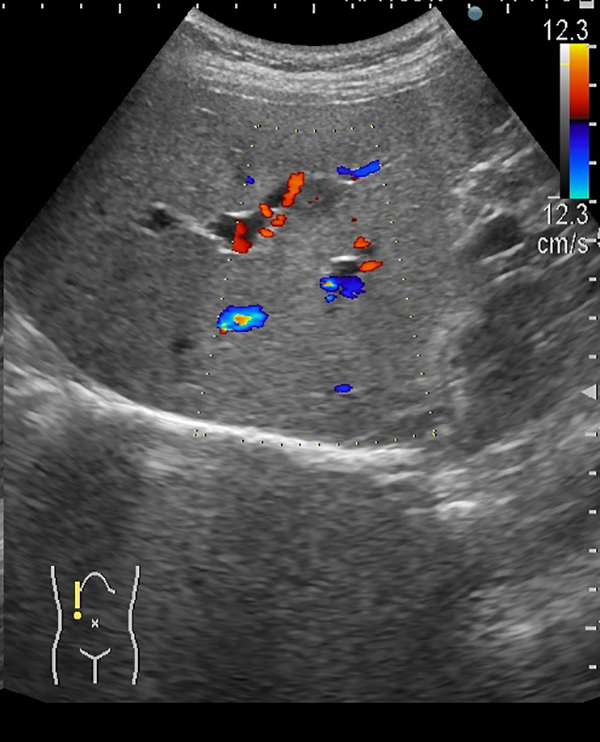

①肝内胆管癌

2. ドップラーエコーで動脈血流を認めました。

3. この時点で径16.9×16.9mmでありステージI期と考えられます。

このサイズで胆管癌が見つかることは非常にまれです。